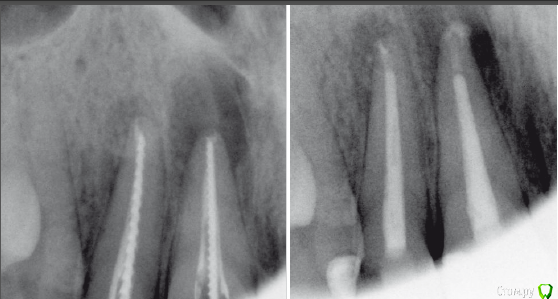

Slaggy Опубликовано 21 декабря, 2015 Поделиться Опубликовано 21 декабря, 2015 Было 06/2015 2 недели - кальций, Апекс- триоксидент, дальше латералка Акросил.Стало 12/2015 Жалоб не предъявляет.Сделать резекцию или пусть живет? Ссылка на комментарий

Fibez Опубликовано 21 декабря, 2015 Поделиться Опубликовано 21 декабря, 2015 Ждите еще полгода. Если не покатит- резекция с ретроградкой. На одном, вроде, улучшение видно. Ссылка на комментарий

Ker Опубликовано 21 декабря, 2015 Поделиться Опубликовано 21 декабря, 2015 имхо - не трогать пока.на обоих стало лучше.если не станет, то перелечить попробовать еще раз. Ссылка на комментарий

Чертков Александр Опубликовано 22 декабря, 2015 Поделиться Опубликовано 22 декабря, 2015 Видно же явные улучшения! Подождите! ...а то нетерпиться за нож схватиться... Ссылка на комментарий

Гарриевич Опубликовано 3 января, 2016 Поделиться Опубликовано 3 января, 2016 Было 06/2015 2 недели - кальций, Апекс- триоксидент, дальше латералка Акросил.Стало 12/2015 Жалоб не предъявляет.Сделать резекцию или пусть живет?Коллега, 6 месяцев это только первый пик заживления, на нем может вообще не быть улучшения или оно может быть незначительным. По совести окончательное решение healing/healed/fail принимается спустя 4! года. Но даже если никакой, ни положительной, ни отрицательной динамики не будет, но при этом зуб будет бессимптомный, то он признается "functional" и живет спокойно без никаких резекций 4 Ссылка на комментарий